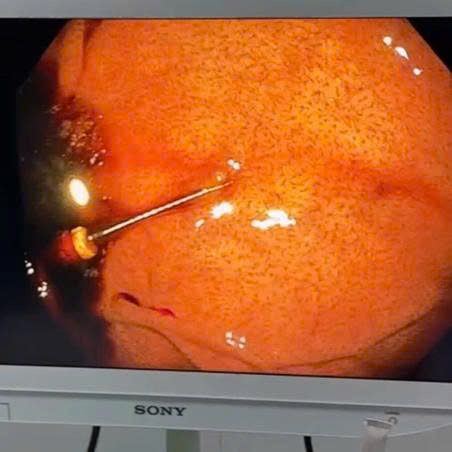

Sau khi thăm khám lâm sàng, khai thác bệnh sử và thực hiện các cận lâm sàng cần thiết, các bác sĩ xác định dị vật nằm trong dạ dày, tiềm ẩn nguy cơ gây tổn thương niêm mạc và biến chứng nếu không được xử trí kịp thời. Bệnh nhân được chỉ định nội soi can thiệp cấp cứu nhằm loại bỏ dị vật sớm, hạn chế tối đa nguy cơ tổn thương đường tiêu hóa

Nhờ hệ thống nội soi hiện đại cùng sự phối hợp chặt chẽ, chuyên nghiệp của ê-kíp bác sĩ, dị vật đã được gắp ra an toàn qua đường nội soi, không cần phẫu thuật. Thủ thuật diễn ra thuận lợi, ít xâm lấn, giảm thiểu nguy cơ biến chứng. Sau can thiệp, tình trạng bệnh nhân ổn định.

Hệ thống nội soi hiện đại hỗ trợ chẩn đoán và điều trị

Bệnh viện Đa khoa Tân Yên được trang bị hệ thống nội soi Olympus CV-190 – hệ thống xử lý hình ảnh cao cấp tích hợp công nghệ NBI và nguồn sáng LED tiên tiến, giúp:

- Quan sát rõ cấu trúc niêm mạc đường tiêu hóa

- Phát hiện sớm các tổn thương tiền ung thư

- Tăng khả năng nhận diện vi mạch bất thường

- Hỗ trợ can thiệp nội soi an toàn, chính xác và hiệu quả